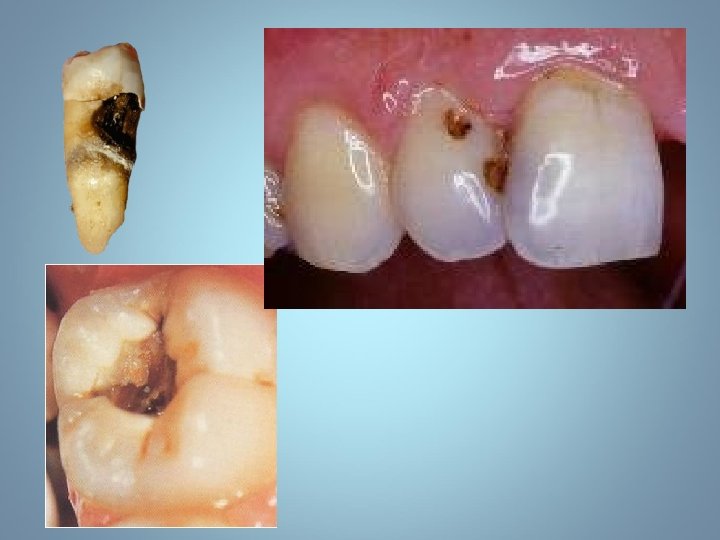

Plus tard • Perte de substance, la carie forme une cavité • La cavité avec des parois ramollies est très caractéristique de la carie.

Parois ramollies

Carie dans la dentine

Détruit des parties de la couronne • Perte du point de contact • Inflammation de la papille inter dentaire • Carie de la surface adjacente • Migration des dents et troubles de l’occlusion

Carie puits et sillons (Classe I)

Carie interproximales postérieures (Classe II)

Caries classe ll

Caries classe II • Évidence radiographique de caries interproximales sur les prémolaires.

Caries interproximales Classe ll